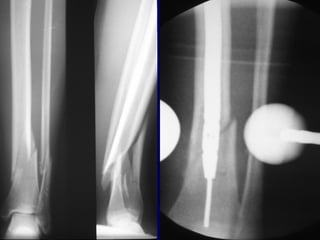

Surgical Options • Intramedullarynail • ORIF with plate • External Fixation

• 40.

Advantages of IMNail • Advantages include less malunion and less shortening than closed treatment or ex-fix • Earlier weight bearing may be allowed with insertion large nail

• 41.

Hooper • In aprospective study found that when displacement >50% and angulation >10 deg. • Nails superior to cast treatment

• 42.

F/U 4.4years Cast Nail •SF36 74 85 • KNEE 89 96 • ANKLE 84 97 • BONE JBJS JULY 1998

Proximal and DistalCases Courtesy of R. Winquist M.D. Seattle, Wa.